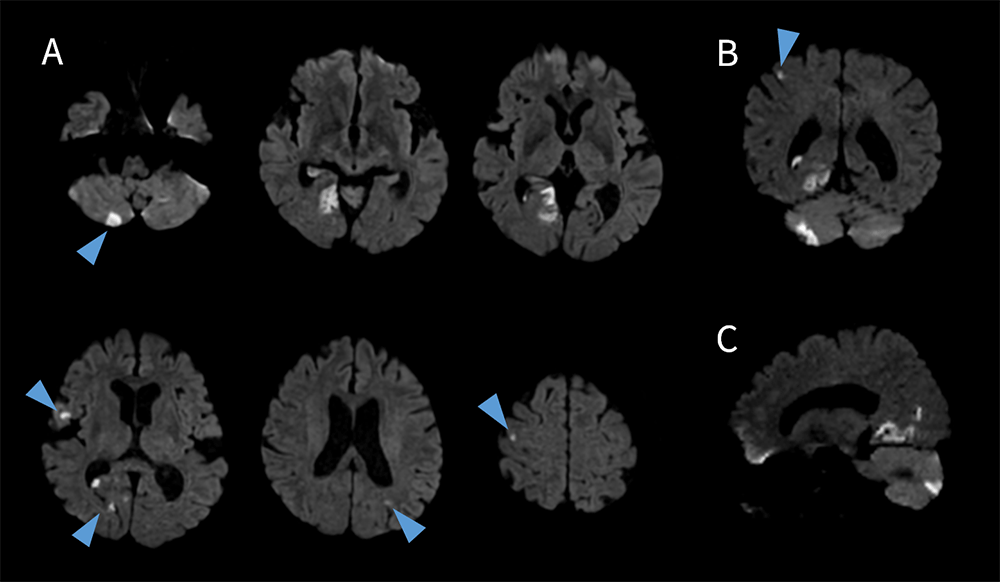

整形外科領域の検査では、多くの撮像シーケンスや撮像断面が必要とされることが多く、加えて手指などの細かい構造物の描出も同時に求められるため、高分解能化に伴い撮像時間が延長することが懸念された。しかしながら、SIGNA™ Primeでは、面内の空間分解能やスライス分解能を向上させることによるノイズ増加が懸念される条件下でも、AIR™ Recon DLによってSNRが十分に担保され、同時に撮像時間の短縮まで可能となる。その結果、短時間かつ高分解能な画像が得られている(図8)。紹介検査においても、SIGNA™ Primeの導入により、以前までは依頼のなかった手指や腫瘍を対象とした検査依頼も増えており検査の幅が広がったと実感している。

Prime_Tamaki_10.png

図8 ガングリオン症例における手指撮像

A. T1強調像 Sagittal スライス厚:1.5mm 撮像時間:2:01 min

B. STIR像 Coronal スライス厚:2.0mm 撮像時間:1:50min

C. T1強調像 Axial スライス厚:2.0mm 撮像時間:1:47min

D. T2強調像 脂肪抑制 Axial スライス厚:2.0mm 撮像時間:1:40min